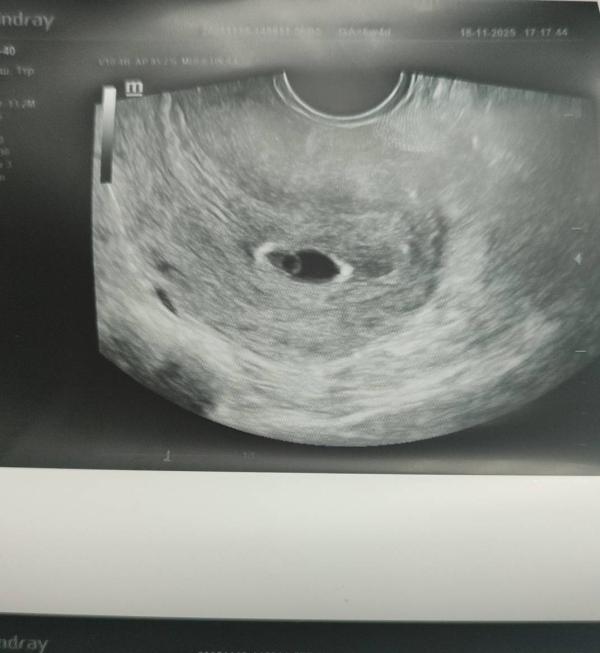

Не увидели сердцебиение на УЗИ: что делать дальше

Сходила на узи. Вобщем, сб не увидели, в остальном все в описании.слава богу, что подтвердили б. Я очень тревожная, жду снова узи

С дочкой в 6.2 уже все было, сейчас в 6.2 не было сердечка, появилось в 7.2 на узи , так как срок с узи отличался на неделю